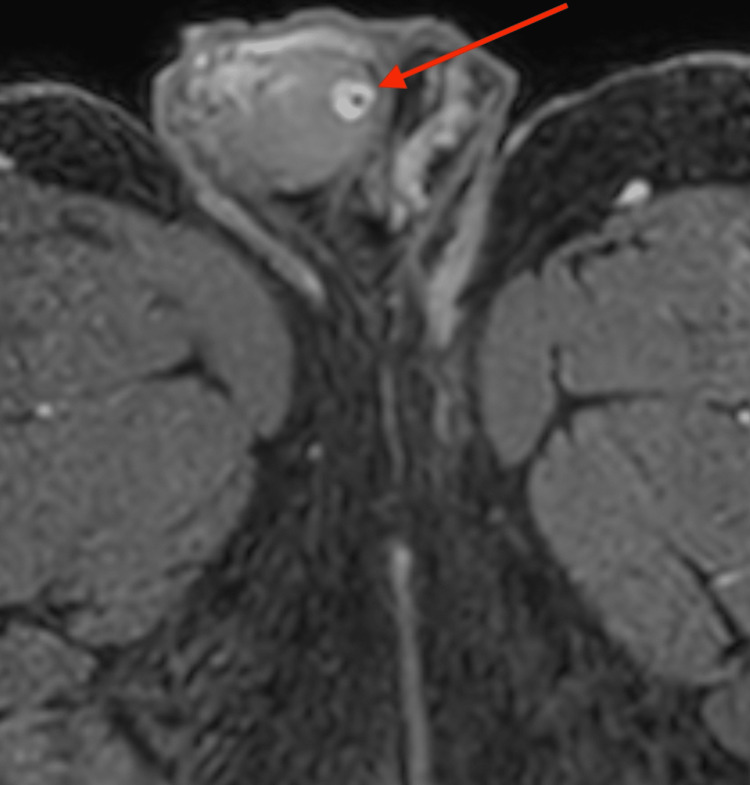

Figure 4. Contrast-enhanced, fat-suppressed T1-weighted transversal MRI of the pelvis.

Image of the scrotum and right testicle and transversal view of both thighs showing a ring-shaped, strong enhancement with contrast medium sparing of the hypo-intense tumor center in the right testicle (marked with the arrow)

An oval-shaped, 8 mm mass underneath the tunica albuginea testis was detected by additional magnetic resonance imaging using a 1,5 Tesla MRI with a surface coil. T2-weighted images revealed an inhomogeneous, hypo-intense mass with a smooth border (Figure 2). In pre-contrast T1W, there was a punctiform signal gap in the center of the lesion (Figure 3). Contrast-enhanced, fat-suppressed T1W imaging showed a ring-shaped strong enhancement with contrast medium sparing of the hypo-intense tumor center (Figures 4, 5). Furthermore, MRI showed a predominantly signal omission in diffusion-weighted imaging (DWI). The right paratesticular structures were normal upon MR imaging while a 2.4 cm spermatocele was detected at the caput of the left epididymis.

Scrotal sonography in our patient clearly showed a round calcified lesion with acoustic shadowing, as well as peripheral vascularization. This unique feature was not consistent with malignant germ cell tumors and thus prompted considering TSS, as also advocated by the current German clinical practice guideline for the management of germ cell tumors [16]. Further support for the assumption of a benign neoplasm came from contrast-enhanced MRI imaging showing a ring-shaped strong enhancement. Al-Obaidy et al. suggest LCCSTs in patients above 25 years old should be considered potentially malignant, therefore inguinal surgical approach should be done [10].